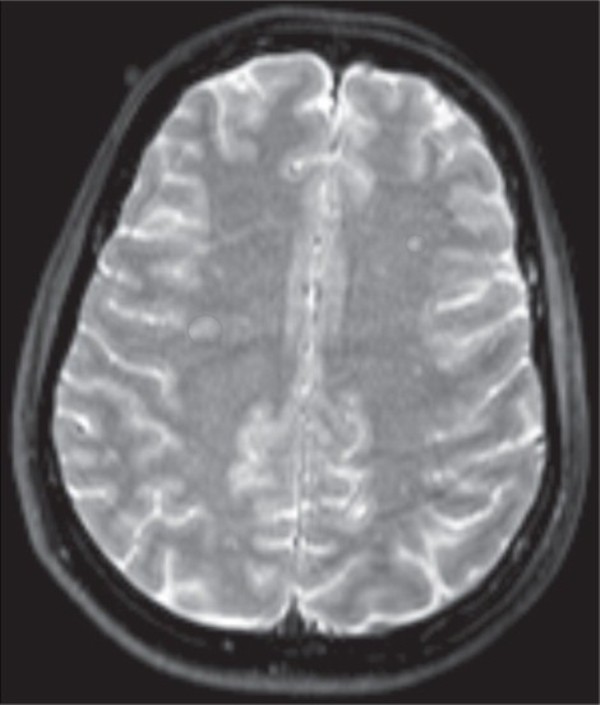

Các bác sĩ đã thực hiện một cuộc kiểm tra thần kinh tổng thể, nhưng nó không giải quyết được gì cả. Phim chụp cộng hưởng từ cho thấy một số tổn thương loang lổ trong chất trắng của não bộ, nhưng không có gì quá đáng để chú ý - không có khối u, không đột quỵ, không có đặc điểm giải phẫu học nào kỳ lạ.

Phim chụp cộng hưởng từ cho thấy một số tổn thương loang lổ trong chất trắng của não bộ